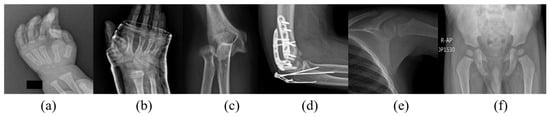

For sophisticated medical procedures and computer-aided diagnosis, segmenting medical images is a crucial preprocessing step, enabling efficient feature extraction by locating key structures that improve diagnostic effectiveness. Extracting anatomical cues from particular ossification centers rather than whole X-ray images greatly increases interpretability and accuracy for age estimation. Nevertheless, as Figure 1 illustrates, medical segmentation in this field remains challenging. These elements highlight the need for a robust segmentation pipeline that can differentiate between soft and hard tissue boundaries with anatomical consistency, enabling the model to learn age-dependent skeletal features more effectively. To address these gaps, the proposed work introduces a comprehensive medicolegal-relevant solution for automated estimation from an Indian perspective. The significant contributions are as follows:

Figure 1.

Image samples of challenging conditions encountered during data acquisition: (a) non-standard pose; (b) plaster of Paris on the ROI; (c) fracture on the ossification joint; (d) implants on the ROI; (e) heterogeneous contrast; and (f) radiological artifacts.